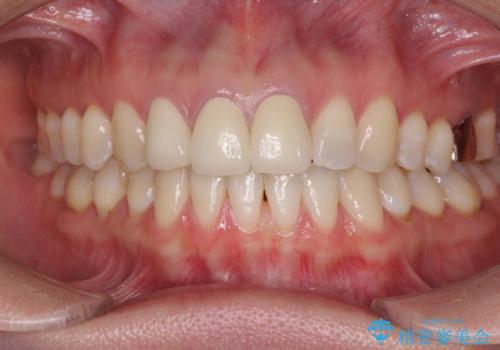

前歯の審美歯科治療 オールセラミッククラウンと部分矯正

- 上の前歯のセラミッククラウンが古くなったことと、下の前歯のデコボコを気にして来院された患者様です。

前歯は一部根管治療を行った後にオールセラミッククラウンに補綴することとしました。

補綴治療に先立ち、下顎前歯の部分矯正を行い、前歯の咬み合わせの安定性向上を図りました。

当初は上顎の補綴治療のみを希望されていましたが、仮歯装着期間に上下の前歯の接触が気になったため、部分矯正を行うこととしました。

審美面と合わせて機能面も改善され、患者様には大変満足していただきました。